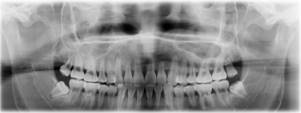

我公司提供多種高性能探測器,適用于CT技術中的各種應用。其中,XUV系列探測器,無需閃爍體,是專為X射線應用設計的探測器件,具有極高的量子效率和低噪聲特性;PIN-RD系列探測器具有大有源面積和高響應速度,適用于高能輻射檢測,這些探測器的耗盡層可以被完全耗盡,以實現最低的結電容和快速響應時間;A2C系列多通道X射線探測器由安裝在PCB上的16個元件陣列組成,本系列探測器可以與多種閃爍體配合使用,將中高能輻射能量轉換為可見光譜。下圖展示了使用我公司多通道X射線探測器獲取的高清晰度牙齒X射線成像表征圖,能夠在使用更低輻射劑量的同時,提供高質量的圖像。